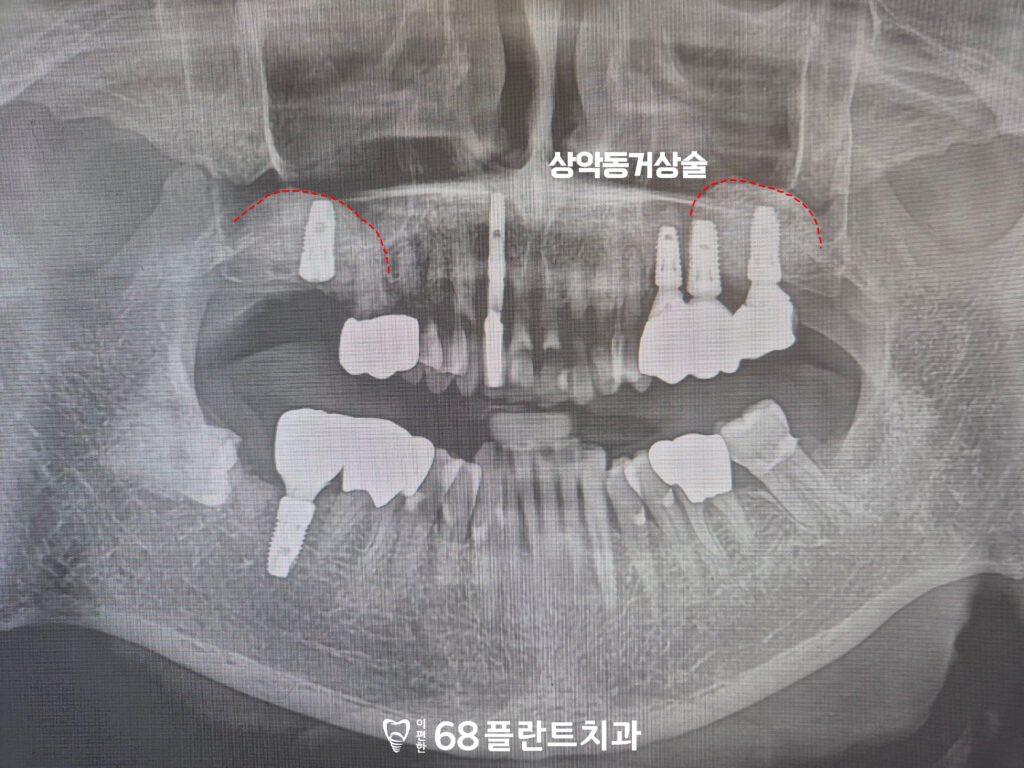

먼저 발치 후 상악동거상술을 진행하여

부족했던 뼈 높이를

충분히 확보했습니다.

위쪽 어금니 부위는 해부학적으로

상악동이 가까워 치아를 잃은 기간이

길어질수록 뼈가 얇아지는 경우가 많습니다.

이 환자분 역시 오랜 결손으로 인해

치조골 높이가 많이 감소해,

임플란트를 안정적으로 식립하기 위해서는

뼈를 보강하는 과정이

필수적이었습니다.

상악동거상술을 통해

임플란트가 버틸 수 있는

튼튼한 기반을 만들어준 뒤,

새로운 뼈가 자리 잡을 수 있도록

충분한 치유기간을 거치는 계획으로

치료를 이어가게 되었습니다.